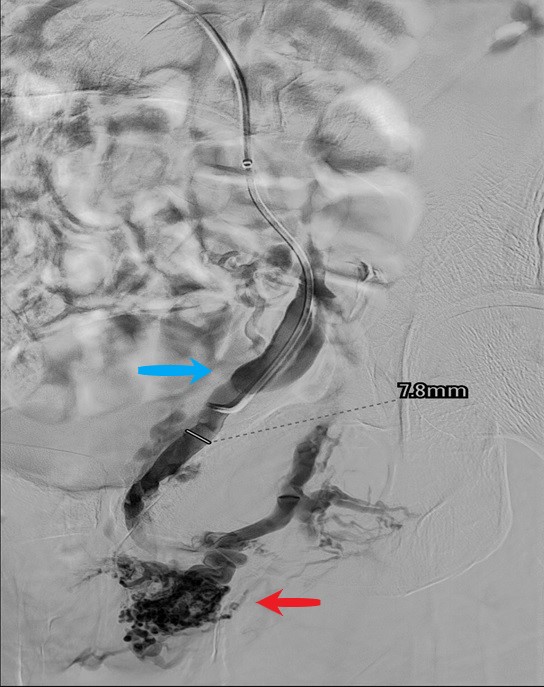

Exemple d'images d'embolisation réalisée dans le service.

Première image, à gauche : phase initiale de diagnostique retrouvant une veine gonadique gauche (flèche bleue) dilatée avec reflux du produit jusque dans les varices pelviennes autour de l'utérus (flèche rouge).